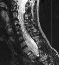

In preparation for spinal fusion for stabilization of this kyphoscoliosis he underwent a MRI of the brain cervical and thoracic spine and CT of the thorax. The brain and cervical spine showed no evidence of tumor. The lower cervical and upper thoracic canal was enlarged without evidence of cord compression, a finding consistent with dural ectasia . There is soft tissue protrusion into the thoracic canal that may resemble a dumbbell lesion.